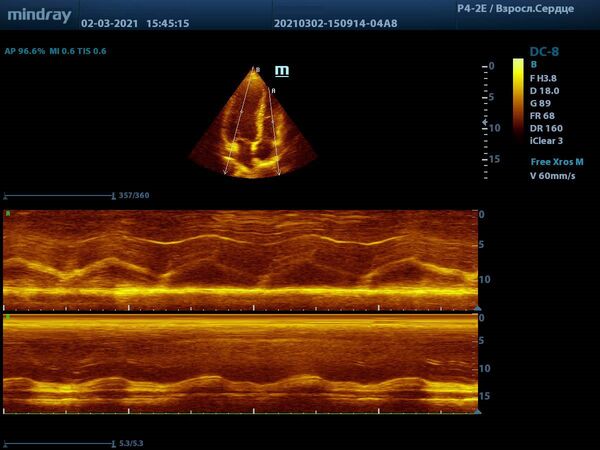

С М-режимом, первым из режимов эхокардиографии, знакомы все. Функцией свободного и анатомического М-режима активно пользуются обладатели машин высокого и экспертного класса. Эти функции используются для оценки створок митрального клапана, формы траектории их движения и амплитуды раскрытия, так же, как и для оценки синуса и полулуний аорты. Современные ультразвуковые диагностические системы компании Mindray, такой как экспертный прибор Mindray DC-8, способны проводить анализ в М-режиме сразу нескольких срезов до 3-х сечений за один раз. Больше не нужно отдельно выводить срез на уровне концов створок клапана и отдельно уровня синуса аорты. Всё получается нажатием пары кнопок и все готово к измерению.

Продвинутые операторы диагностической техники также владеют методами оценки функции желудочков в режиме Free Xros – свободном М-режиме. Такие параметры как TAPSE позволяют быстро и удобно оценить сократительную функцию правого желудочка, нормальное значение движения амплитуды кольца трикуспидального клапана 17 миллиметров или более.

Левый желудочек не остается в стороне, для него есть показатель MAPSE – измеряется в М-режиме и пересчитывается во фракцию выброса левого желудочка. Показатель более 10 мм считают нормой. Для расчета фракции необходимо подставить значение в формулу EF = 4.8 × MAPSE (mm) + 5.8. Такой способ оценки применяется только у взрослых. Использование нескольких срезов одновременно с функцией Free Xross позволит оценить сразу оба желудочка, что сильно экономит время и силы к концу трудового дня.